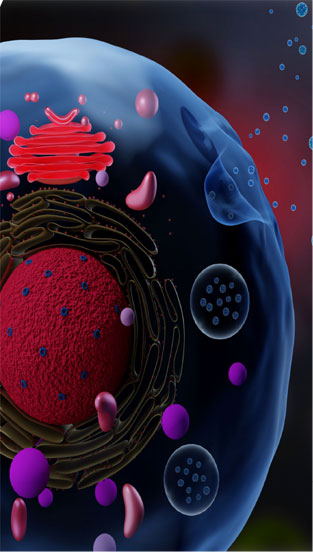

Exosomes are taken from MSC or Mesenchymal stem cells. These stem cells are unique in the human body in that they have the power to differentiate. While all other cells divide and replicate, producing a new cell of precisely the same kind as the original, MSC cells are able to become any type of cell at all.

外泌体取自 MSC 或间充质干细胞。 这些干细胞在人体中是独一无二的,因为它们具有分化的能力。当所有其他细胞分裂和复制产生一个与原始细胞完全相同的新细胞时,MSC 细胞完全能够成为任何类型的细胞。